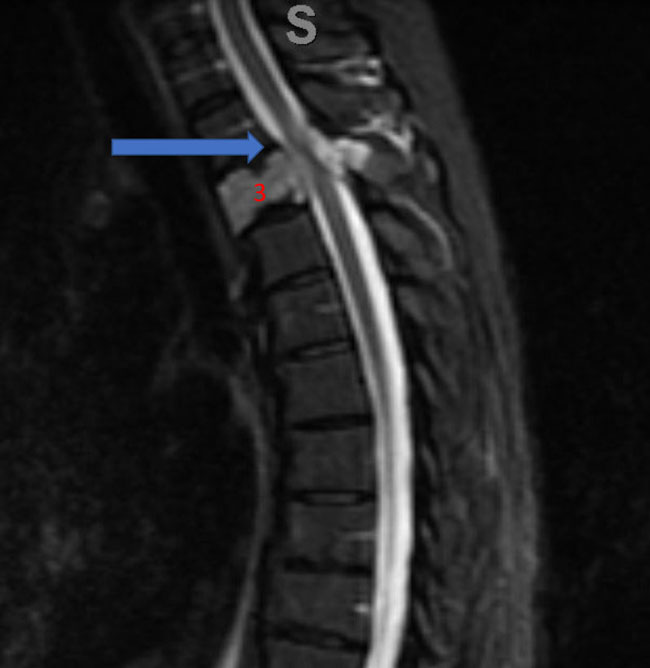

No spinal artery contributions were found to arise from this right T1-T3 pedicle. Superselective WADA testing was performed with Brevital injected through the microcatheter, which failed to elicit changes in the intraoperative monitoring, confirming safety to proceed with devascularization of this pedicle and tumor. This was performed with 100-300 micron particles achieving an excellent devascularization (Figure 3. A, B).

Figure 3. A and B) demonstrates selective PVA embolization with complete devascularization of the tumor on completed embolization.